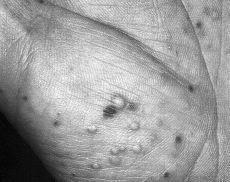

Varón de 52 años, fumador de 20 cigarrillos/día, con antecedente de hipercolesterolemia tratada con genfibrozil. No refería antecedentes personales ni familiares de psoriasis. Consultó por presentar una erupción cutánea pustulosa de 3 días de evolución, que se localizaba en las manos y los pies. Siete días antes del comienzo de la erupción había recibido amoxicilina-clavulánico 500/125 mg cada 8 horas por vía oral para tratar una faringoamigdalitis. La exploración física evidenció la presencia de pústulas no foliculares de 3-5 mm de diámetro rodeadas de un halo eritematoso. Las pústulas se localizaban fundamentalmente en el dorso de manos (Fig. 3) y pies, en los antebrazos, así como alguna lesión aislada en el tronco. No se observaron lesiones en las mucosas. El estado general era bueno. En los análisis destacaron una VSG de 24 mm a la primera hora y un título de ASLO de 1/650. El hemograma y la bioquímica de sangre y orina no mostraban alteraciones significativas. El cultivo del pus obtenido de una pústula fue negativo. El estudio histológico de una lesión mostraba una pústula subcórnea de predominio neutrofílico, con un discreto infiltrado linfocitario perivascular y mínima espongiosis.

FIG. 3.--En el caso 3 las lesiones eran más numerosas. Observamos que las pústulas estaban localizadas sobre piel normal y con un discreto halo eritematoso alrededor.